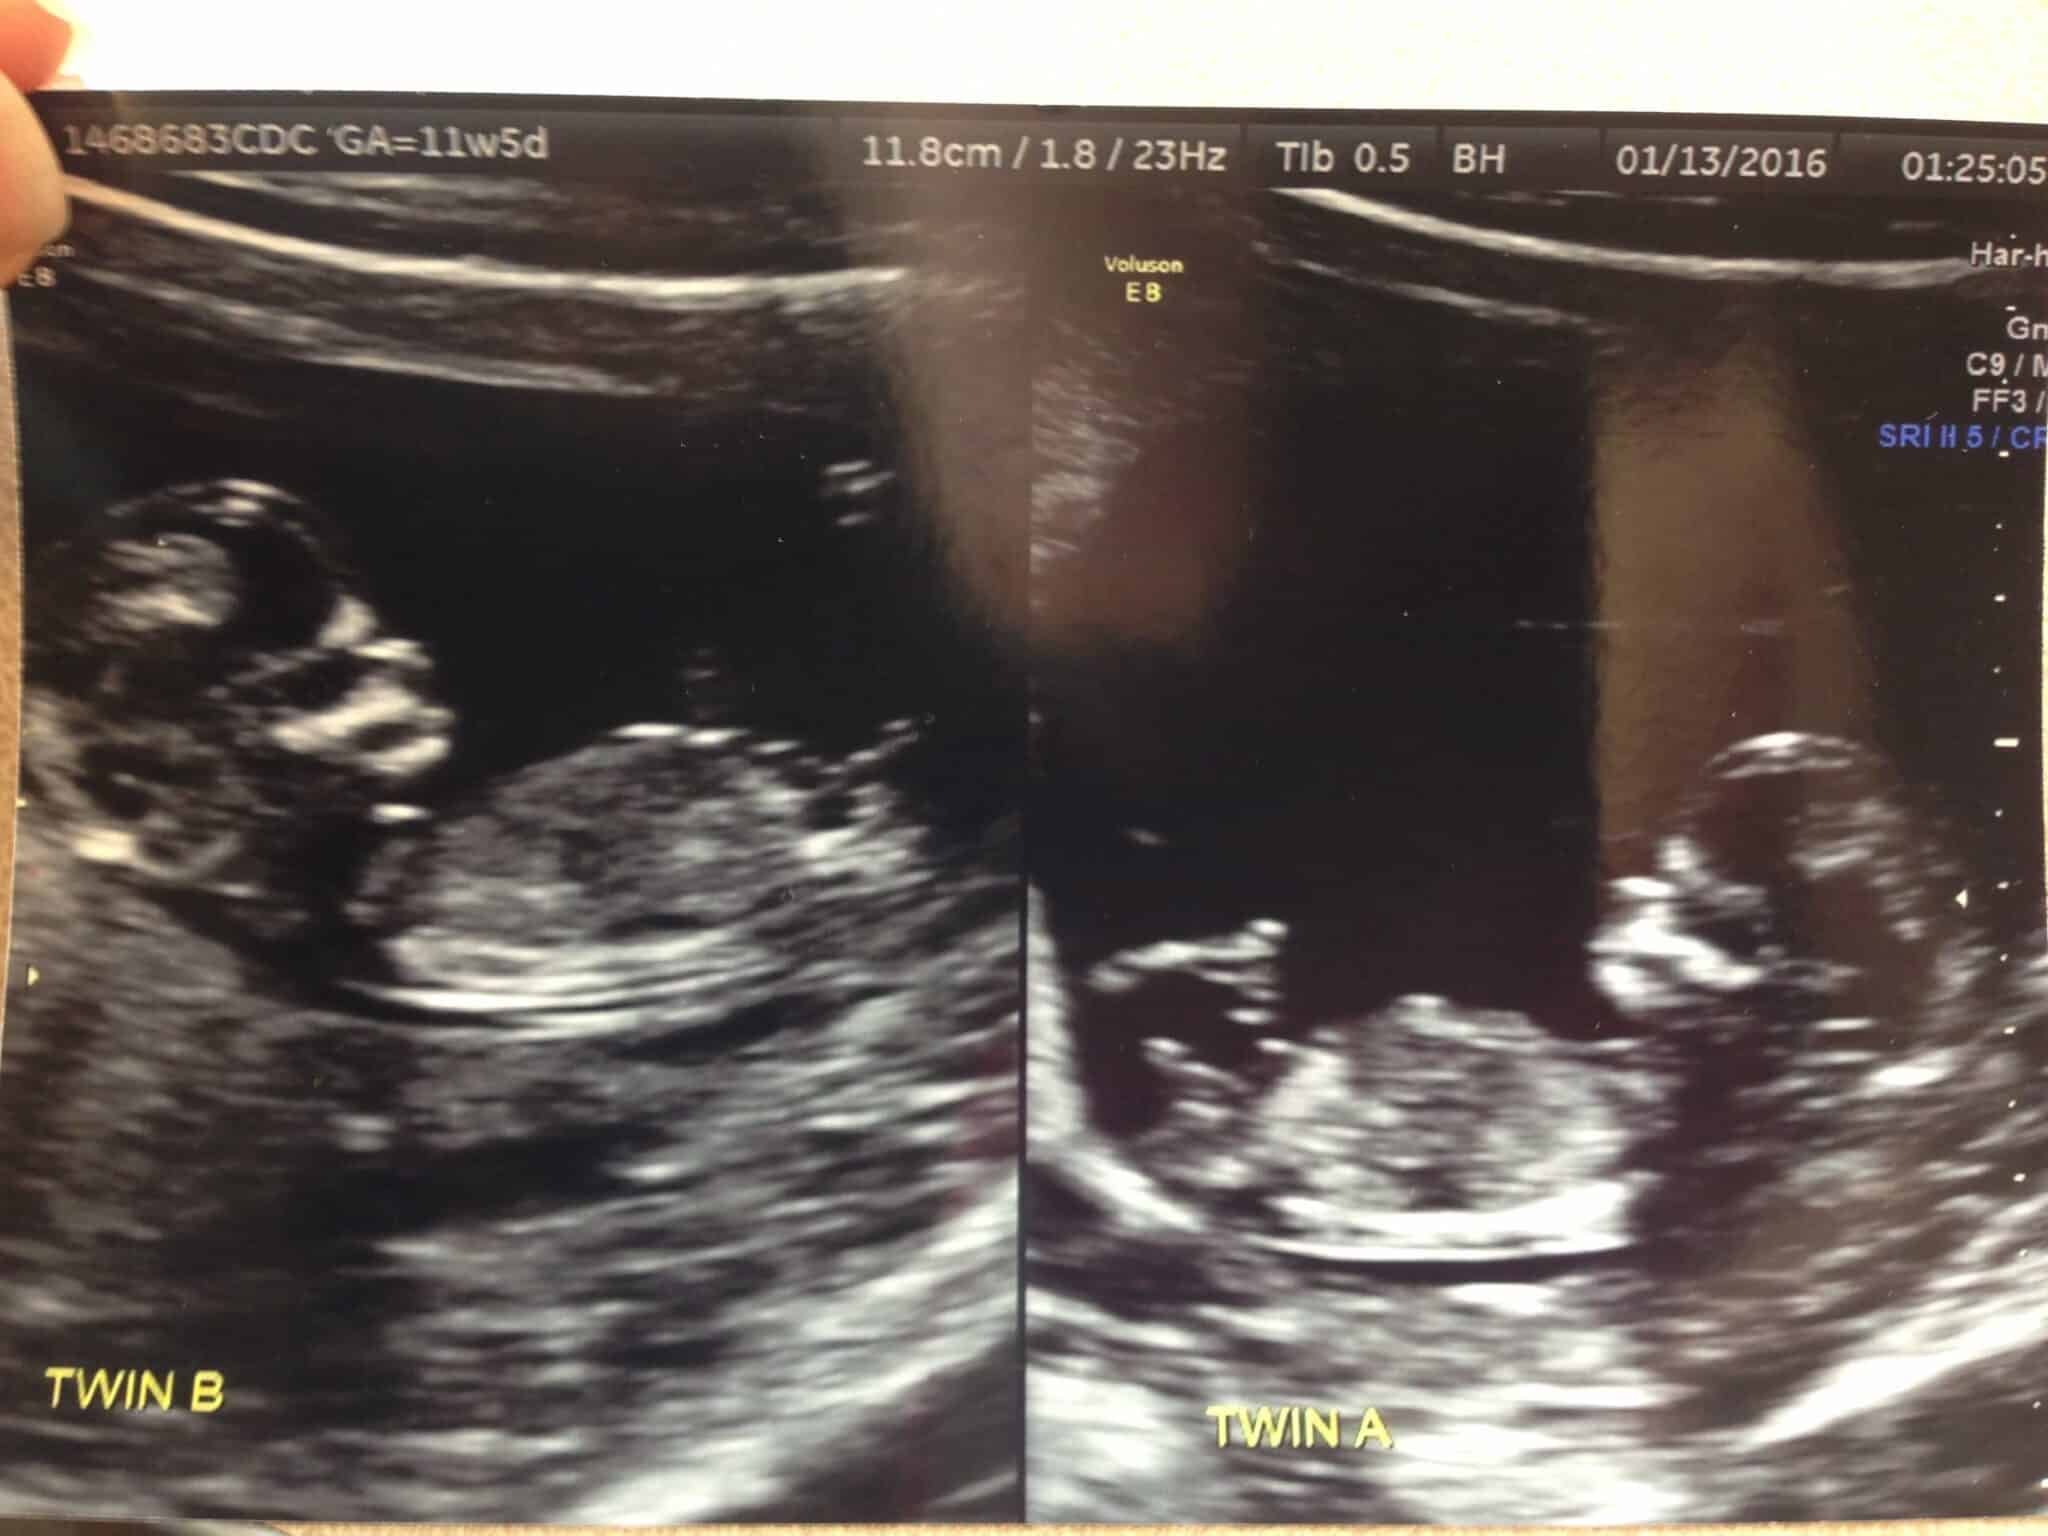

Ultrasound Photos at 12 Weeks Pregnant With Twins